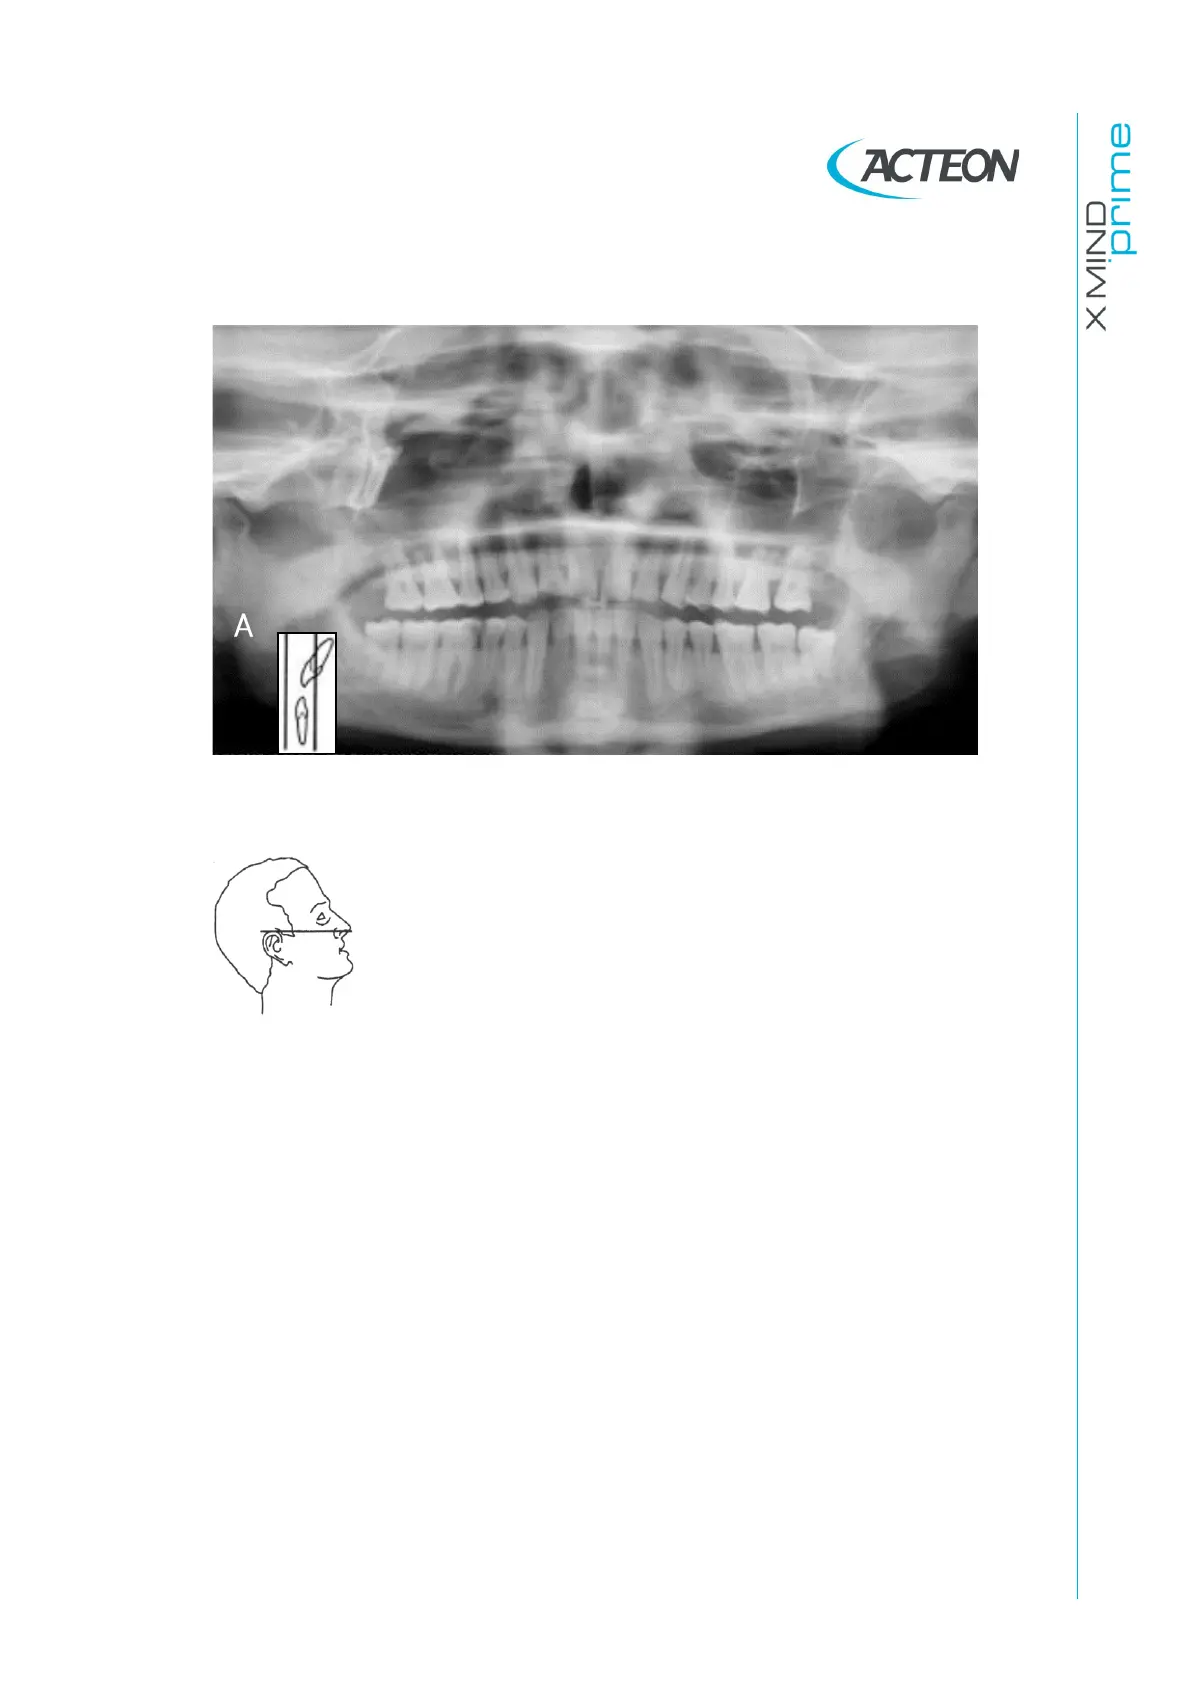

11.2.4 Backward angulation of the head

Figure 37

Problem

The Frankfurt plane is tilted backward.

Effects

The roots of the maxillary anterior teeth are positioned

outside the focal trough so it is out-of-focus and blurred.

The hard palate is superimposed over the apices of the

maxillary teeth.

Both condyles may be off the edges of the image area.

The upper incisors can be blurred.

Flattening of the occlusal plane.